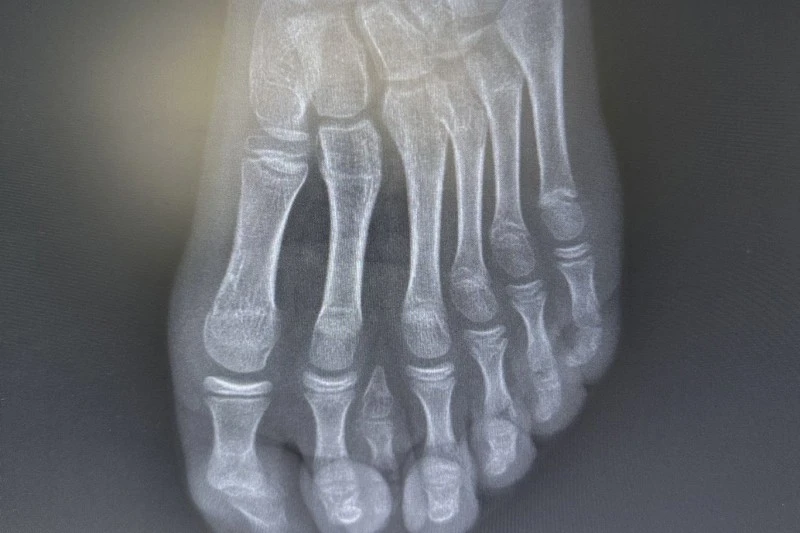

Genel yaklaşımda bu tür vakalarda cerrahi planlamanın ayağın beş parmaklı anatomik yapı sına uygun şekilde yapıldığı ifade edildi. Ancak hastanın yapılan detaylı klinik ve radyolojik değerlendirmelerinde altı parmağın; falanks (parmak kemikleri), metatars (tarak kemikleri) ve diğer ayak kemikleri ile uyumlu ve düzgün şekilde geliştiği tespit edildi.

Uzmanlar, mevcut altı parmağa müdahale edilmesinin ayak biyomekaniğini ve dengesini olumsuz etkileyebileceğini değerlendirdi.

Bu doğrultuda cerrahi planlama yeniden yapılarak, fonksiyonel açıdan yetersiz ve estetik olarak problem oluşturan tek parmağın çıkarılmasına karar verildi. operasyon sırasında diğer parmaklara ait damar ve sinir yapıları titizlikle korunurken, mikrocerrahi teknikler kullanılarak işlem sorunsuz şekilde tamamlandı.